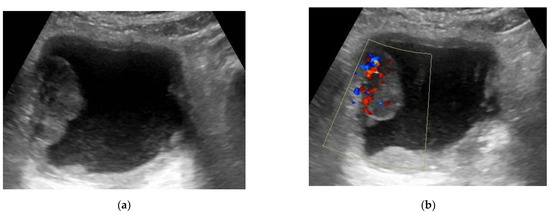

2.3.1. Conventional Ultrasonography

2.3.2. Color Flow Doppler Ultrasonography